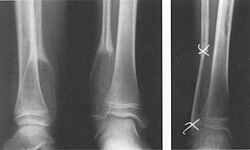

- Einfache (juvenile) Knochenzyste: Gutartige, primär einkammerige, flüssigkeitsgefüllte Höhle, meist im metaphysären Markraum. Wird meist erst durch Spontanfraktur auffällig. Klassisches Röntgenzeichen ist das Fallen-Fragment-Sign.

X-Ray of simple (juvenile) bone cyst with fallen fragment sign | Eigenes Werk | Kinderradiologie Olgahospital Klinikum Stuttgart | Datei:JKZ.jpeg | |